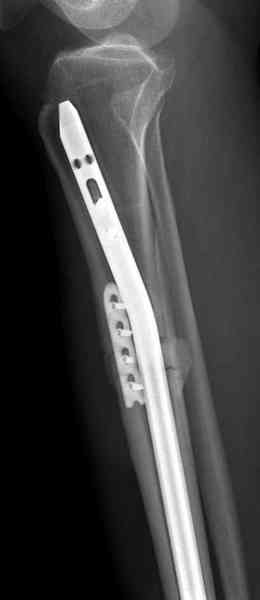

Не оригинальное, подход не раз был демонстрирован нас в стране проф. Анатолием Федоровичем Лазаревым (ЦИТО), который это называет "металлокаркасная пластика". У нас в институте в другом отделении он

помогал сделать несколько таких металлокаркасов, только, насколько я помню, без блокируемых стержней. А в мире эта методика довольно давно

применяется, хотя и не массово. Например, осенью прошлого года на конференции общества Кюнчера в Страсбурге было хорошее сообщение на эту тему. 17 больных, результаты уже до 5 лет.

gt> Was this titanium cage custom made for this patient or commecially

gt> available for such work? Do you have different lengths of this cage or

gt> were you forced to cut it on table to suite tha gap? (Or did you have

gt> to make the gap to suite the cage?)

The cages are commercially available but up to 10 cm. So we measured the needed length on x-rays, added 2 cm at both ends for sure that

the resected piece will include all, and resulted with 15 cm which one was ordered and individually made by the same factory. So yes, we made the gap to fit the cage.

gt> Do you fill the cage with bone graft or are you depending on this

gt> metal for long term support without biological augumentation?

The inner diameter of the tube is 13 mm, the nail was 12 mm, so not so much space to put something inside. Yes, this is really shaft endoprosthesis which i hardly ever would offer for a young football player. Though... Maybe we would when we collect some experience with this sort of implants to feel/prognose its strength in different settings.

gt> How is the skin coverage after such an extensive dissection and

gt> placment of a large piece of metal in a plane very close to the

gt> surface?

No problem with the skin since the cage is less than the removed tissue and the surgery was quick enough not to meet oedema.